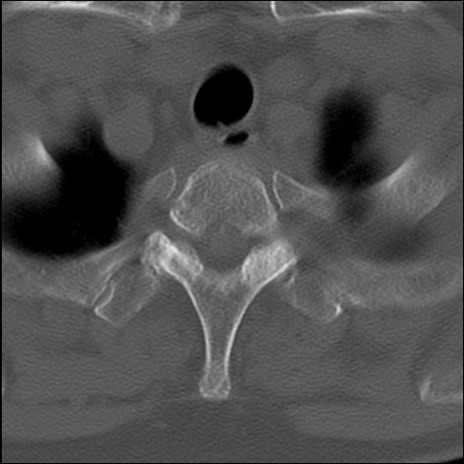

症例48 頚椎CT(横断像)

頚椎CT